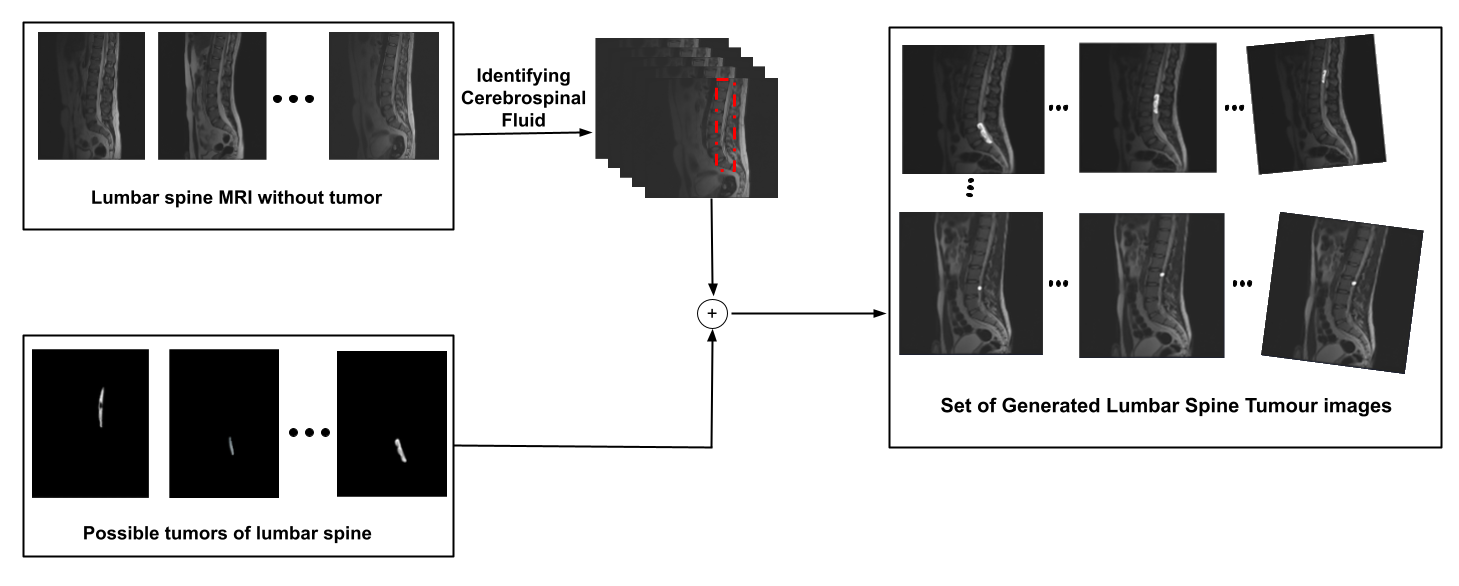

We used a novel data augmentation process shown in Figure 2. First, we extracted the tumors from each slice to collect the different types of tumors. Then, we identify the cerebrospinal fluid in each slice based on a predefined mask. Next, we add a tumor of each type in each slice starting from T11 and slide it one slice at a time, along the cerebrospinal fluid from T11-L5. The size of the tumor in each slice is decided by the size that was originally in a corresponding slice. Thus we have 2D MRI scan slices of the lumbar spine, each depicting a tumor. To account for potential slight rotation during image capture, we deliberately rotated the images by an angle lying between 1 and 10 degrees to the left and the right. This strategy effectively doubled our dataset, providing us with an increased abundance of 3D MRI data for the lumbar spine.

Refer to caption

Figure 2: Flowchart for Proposed Data Augmentation Technique.